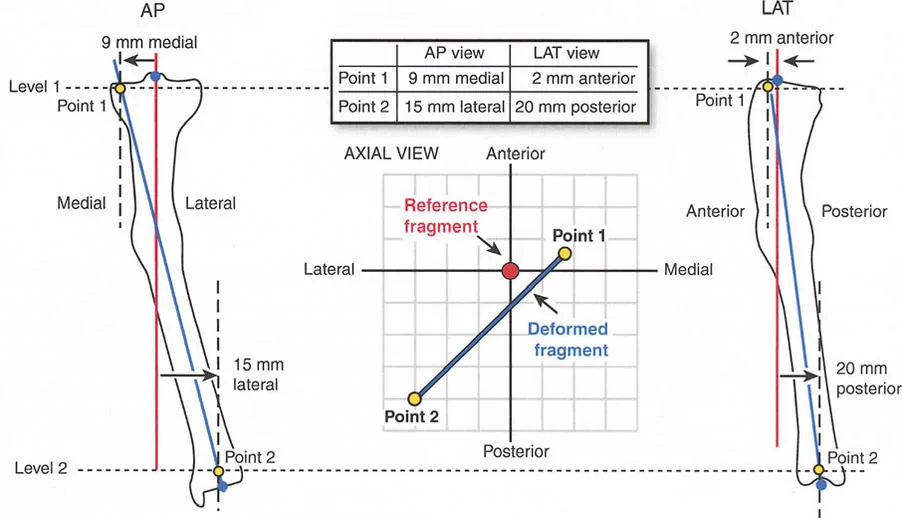

إتقان معدلات الشد: قاعدة المثلثات المتشابهة

القاعدة الذهبية البيولوجية لتوليد العظم بالشد، التي وضعها إليزاروف بعد عقود من التجارب على الحيوانات والبشر، هي معدل شد يبلغ 1 ملم يوميًا. يتم تقسيم هذا عادة إلى زيادات قدرها 0.25 ملم كل 6 ساعات لمحاكاة النمو المستمر للوحة النمو.

ومع ذلك، فإن الخطأ الشائع، الذي قد يكون كارثيًا أحيانًا للجراحين المبتدئين، هو سوء فهم أين يجب أن يحدث هذا الـ 1 ملم يوميًا.

معدل 1 ملم/يوم ينطبق بشكل صارم على القشرة المقعرة للعظم في موقع قطع العظم (الحافة الأمامية للإسفين المفتوح). نظرًا لأن الجهاز (قضيب الشد أو دعامة TSF) يقع على مسافة من العظم، خارج غلاف الأنسجة الرخوة، فإنه يتحرك على طول قوس أكبر بكثير. إذا وجهت المريض لشد القضيب بمعدل 1 ملم يوميًا، فإن العظم الفعلي سيُشد بجزء ضئيل من هذا المعدل، مما يؤدي إلى التصلب المبكر لموقع قطع العظم.

حساب معدل الشد الحقيقي

لحساب المعدل الصحيح للشد عند المفصلة، نستخدم قاعدة المثلثات المتشابهة، والتي تعتمد أساسًا على القاعدة الهندسية للدوائر متحدة